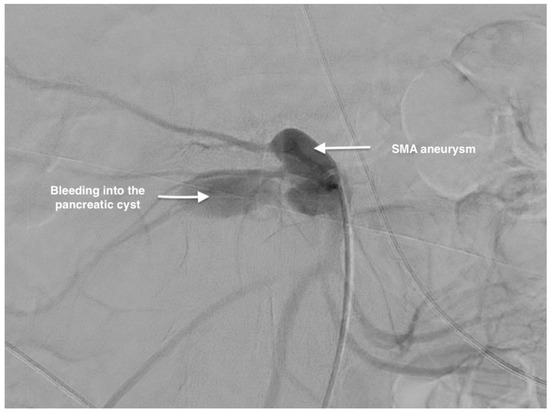

Management of a Rare Case of Superior Mesenteric Artery Aneurysm Associated with a Pancreatic Cyst Complicated by Acute Rupture: A Case Report and Review of Literature

2. Case Report